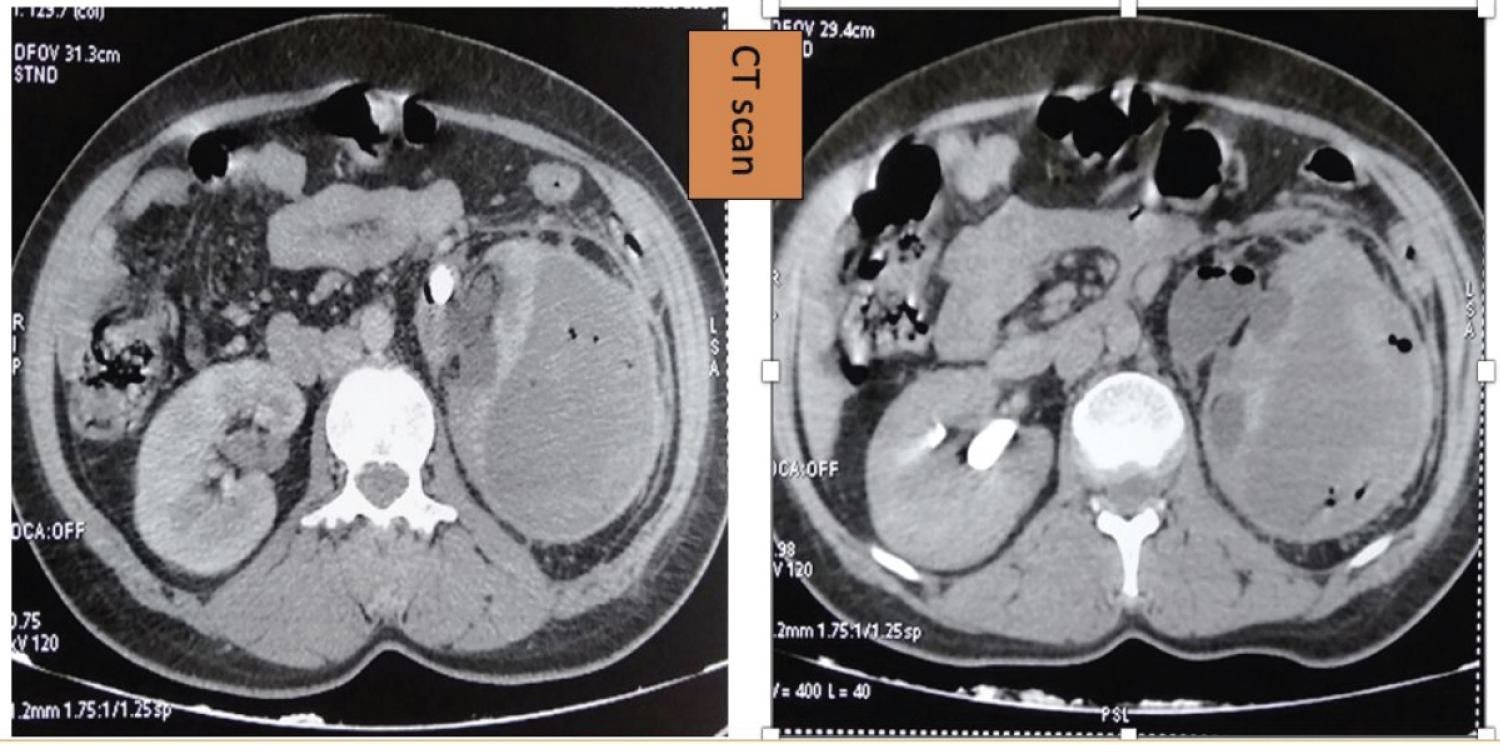

We report the case of a 41-year-old female patient, a known diabetic on insulin, who presented to the emergency department with left lumbar pain evolving for 3 days in a febrile context. She also reported irritative urinary signs associated with cloudy urine. On admission, performance status was 2, the patient was conscious with a temperature of 38.9 ℃ and significant pain on palpation in the left lumbar fossa. Emergency blood tests revealed an inflammatory syndrome and impaired renal function. Standard radiography revealed a stone in the left renal area. CT scan (Figure 1) revealed an enlarged kidney with pyelocalic dilatation upstream of a pyloric calculus, and a heterodense subcapsular perinephric collection of hematic density and multiple air bubbles. This collection measures 6 cm thick medially. There is also extensive infiltration of peri-renal fat. Emergency treatment consisted of a venous line and antibiotic therapy with ceftriaxone and amikacin, adapted to her renal function. She was rushed to the OR for a double-J catheter (purulent urine) and percutaneous nephrostomy. The final outcome was favorable, with improvement of clinical signs and normalization of biological parameters.

Figure 1: CT sections showing a hypertrophied kidney with pyelo-caval dilatation upstream of a pyloric calculus, and a heterodense subcapsular perinephric collection with patches of hematic density and multiple air bubbles.